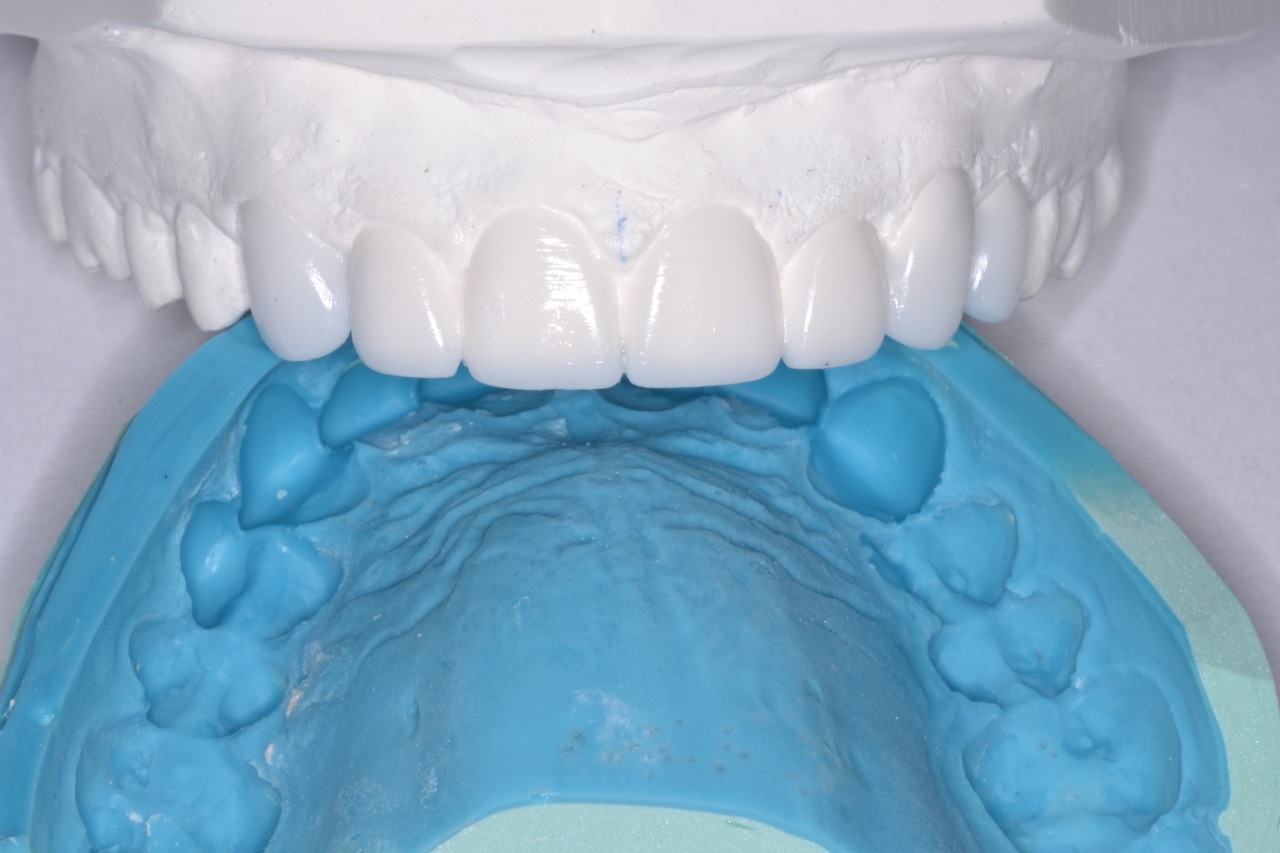

Sally started soft tissue therapy while I worked with my lab to create an idealized diagnostic wax-up and refractory putty matrix. (Fig. 2) At her pre-op hygiene visit, she presented with healthy tissue, and upon seeing the smile design wax up, she was quite emotional.

Figure 2

Figure 2. Shows idealized wax-up and refractory putty matrix